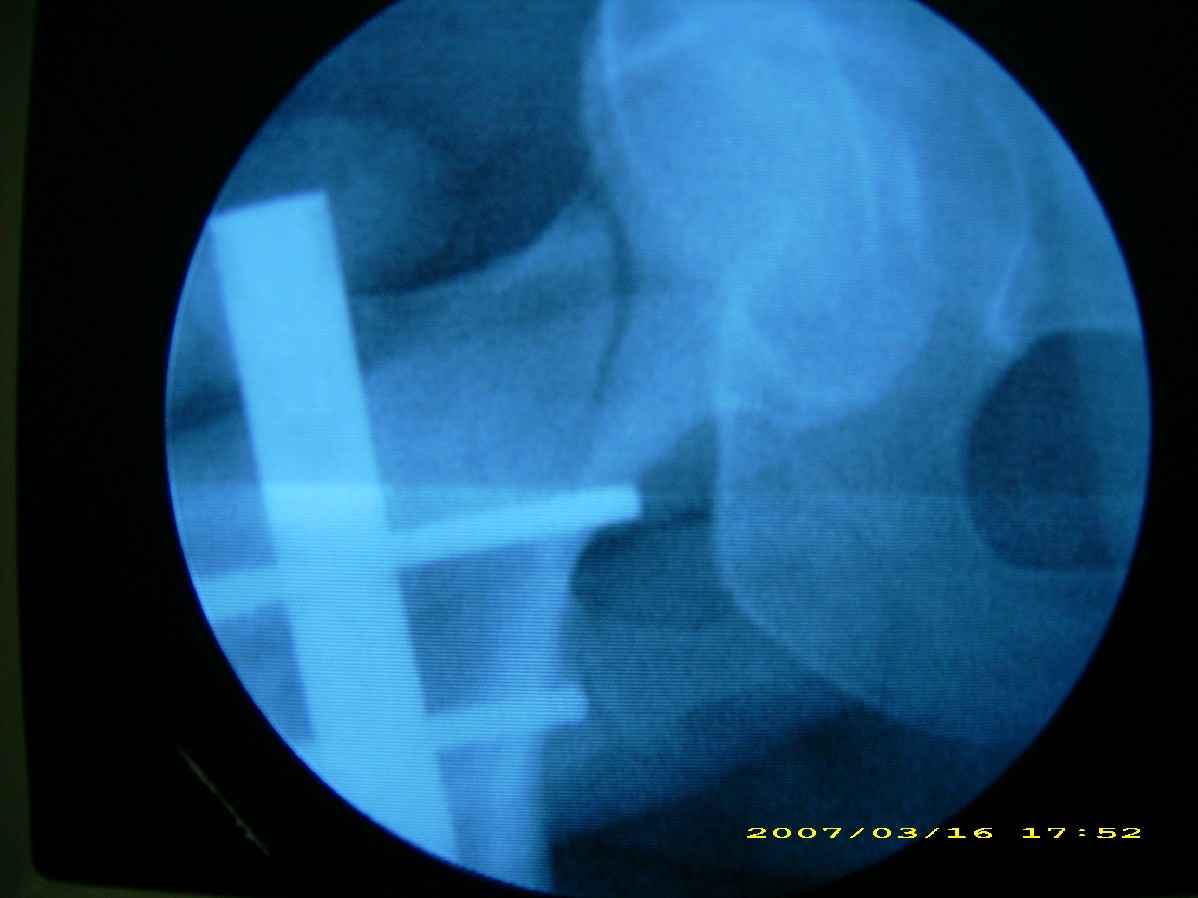

患者,女,因外伤就诊。摄骨盆及右股骨。当时报告骨盆未见明显异常,右股骨中段粉碎性骨折。五天后行股骨中段骨折内固定手术,术中摄床边片示股骨颈骨折。现把术前和术中图像上传。请大家高诊,分析股骨颈骨折是术前漏诊还是其他原因。术前骨盆片右股骨颈显示欠佳是由于股骨中段骨折无法将股骨颈完全显示。

现在我向大家请教,股骨中段粉碎性骨折的同时股骨颈也会骨折吗,另外如图所示该患者股骨颈骨折线是我们常见的由外伤引起的骨折线吗。